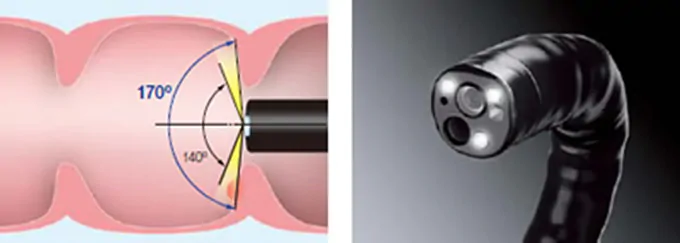

ワイドアングル

最新鋭の内視鏡スコープでは、観察可能な視野角が大幅に広がりました。これまでの大腸カメラでは内視鏡の観察範囲が前方140度であったのに対し、最新鋭の内視鏡においては30度広がり、170度になりました。

これにより従来の内視鏡スコープでしばしば死角となり、見逃されていた大腸のひだの後ろに隠れた病変の見落としがほとんど無くなりました。